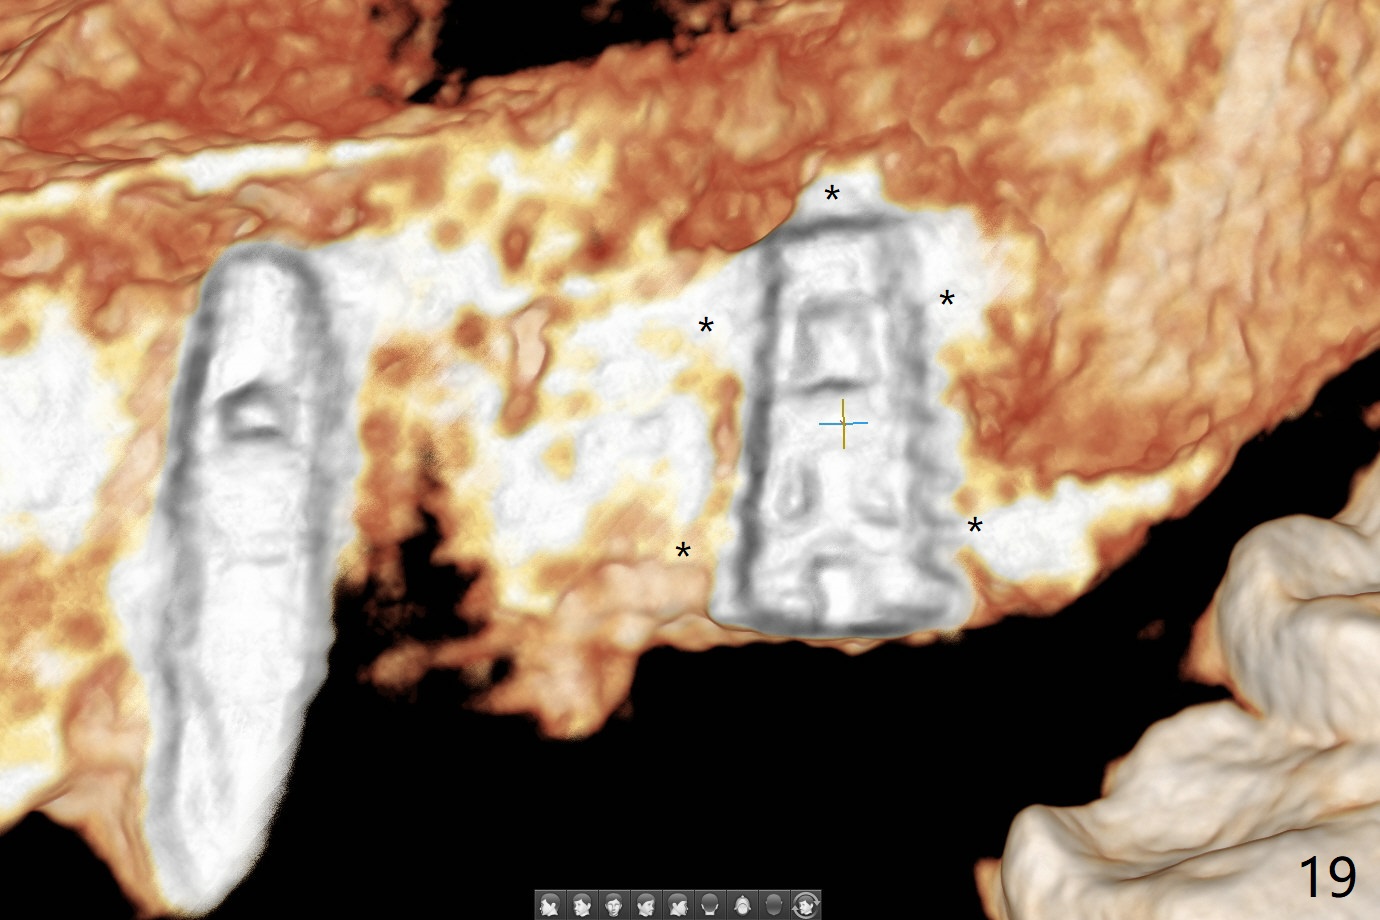

Osteotomy at #13 starts blindly (no incision or tissue punch) with bone expanders. After insertion of parallel pins, intraop CT shows that it is palatal with apparently buccal low bone density (Fig.1); the osteotomy for implant (Fig.2 green) should be shifted buccal and tilted mesial (red, parallel to #11) with incision. In contrast the position, trajectory and depth (Fig.3 <) of the initial osteotomy are acceptable at #11. The implant will be placed as it is (Fig.4). After taking a postop PA (Fig.5), the implant at #11 is placed a little deeper to make sure its slightly subcrestal placement (including distal incision at #11). Following placement of 3.5x4 and 3 mm ball abutments at #11 and 13, cortical allograft with PRF is placed around the implants, especially buccal (Fig.6,7 <). After suturing, the profile of the ball abutments is too low for RPD retention. Due to gravity other than bone density, the number of ball abutments for the maxilla should be more than for the mandible. Soft reline is done to the patient's satisfaction. The retention of the upper RPD after soft reline is satisfactory without pain 7 days postop (Fig.8). The implant at #13 is loose nearly 3 months postop (Fig.9 *: bone loss). The implant is removed while the ball abutment is untightened; the sinus floor is present. It appears that a longer and larger implant is necessary; a 4.5x10 mm dummy implant is unable to be seated deep or achieve primary stability (Fig.10). After sinus lift with 3 mm Bicon osteotome without bone graft, the dummy implant accomplishes the 2 tasks mentioned above (Fig.11). However there is no corresponding definitive implant in stock. Implant system needs to be changed; with a change in implant driver, the depth control is lost. The final implant is placed deep (Fig.12). With back up, stability is lessened; a healing screw is placed; with collagen plug, the wound is sutured (Fig.13). The wound heals 1 week postop (Fig.15). The RPD is soft relined. Retention from the ball abutment at #11 is apparently critical. The RPD and #11 implants (4 months postop) are stable, while the wound at #13 heals 1.5 months postop (Fig.15). There is space around the implant 5.5 months postop (Fig.16 *). The 5x10mm SM implant is found to be loose upon uncover and removed. After debridement, 5.3x8 mm SM and 5.5x9 mm IBS dummy implants are inserted without stability, while 6x9 mm definitive one with stability (Fig.17). Cortical allograft is placed in deficiency areas (*). The osteotomy has no roof (sinus floor), but the sinus membrane is intact. Small amount of bone graft (Fig.18 *) is placed before implantation. There appears to be bone around the new implant (Fig.19 (3D sagittal section) *).